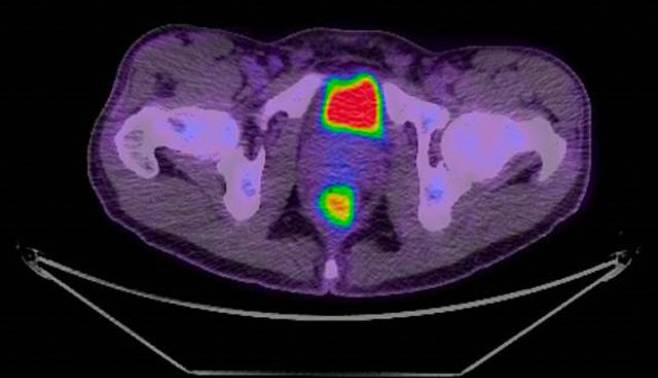

کمک به بیماران مبتلا به سرطان خون با اسکن های هوشمند PET/CT

پژوهشگران استرالیایی در تحقیقی که بر روی بیماران مبتلا به سرطان خون انجام داده اند، [...]